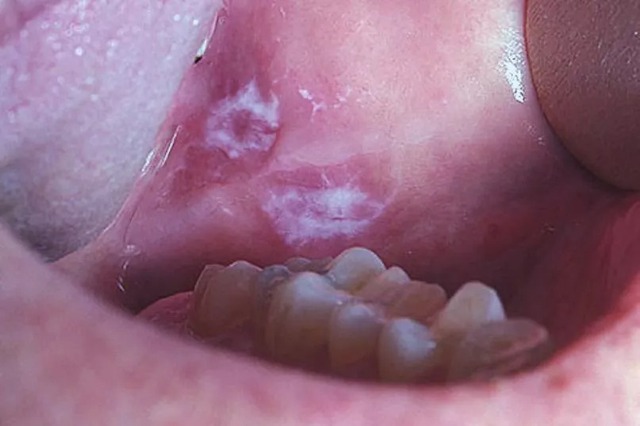

Trước khi phát triển thành vết nhiệt miệng rõ ràng, ung thư khoang miệng có thể bắt đầu bằng các tổn thương tiền ung thư (tiền ác tính) dưới dạng mảng màu bất thường, thường bị nhầm lẫn với nấm hoặc đổi màu niêm mạc.

Ảnh minh họa

Cụ thể là các mảng trắng (Leukoplakia) có màu trắng xám, dày, thường không gây đau, hoặc các mảng đỏ (Erythroplakia) có màu đỏ tươi, nhung. Nếu bạn nhận thấy bất kỳ mảng trắng hoặc mảng đỏ nào không thể cạo đi được và không biến mất trong vòng 2 tuần, cần phải đi kiểm tra ngay lập tức. Đây là dấu hiệu cảnh báo sớm nhất của sự phát triển tế bào ác tính.